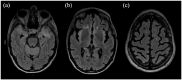

Results: The patient developed subacute cognitive decline with magnetic resonance imaging (MRI) evidence of extensive brain white matter lesions. In the hypothesis of an opportunistic brain infection, she underwent brain biopsy of the temporal pole. Pathology results revealed typical NMOSD findings with complement activation, supporting the hypothesis of an atypical presentation of anti-AQP-Ab-associated NMOSD. Accordingly, treatment with the complement-targeting drug eculizumab was started, leading to a dramatic clinical and MRI improvement.